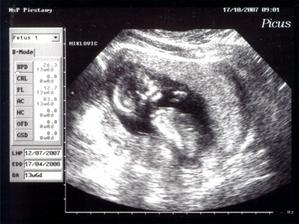

Emuška

Ahojte už som tu z 1,5cm som vyrástla na takúto krásnu slečnu moje meno je Emka a narodila som sa 4.4.2008 o 12:25 hod v Topolčianskej nemocnici vážila som 3510g a najviac na svete ma ľúbia maminka a ocinko